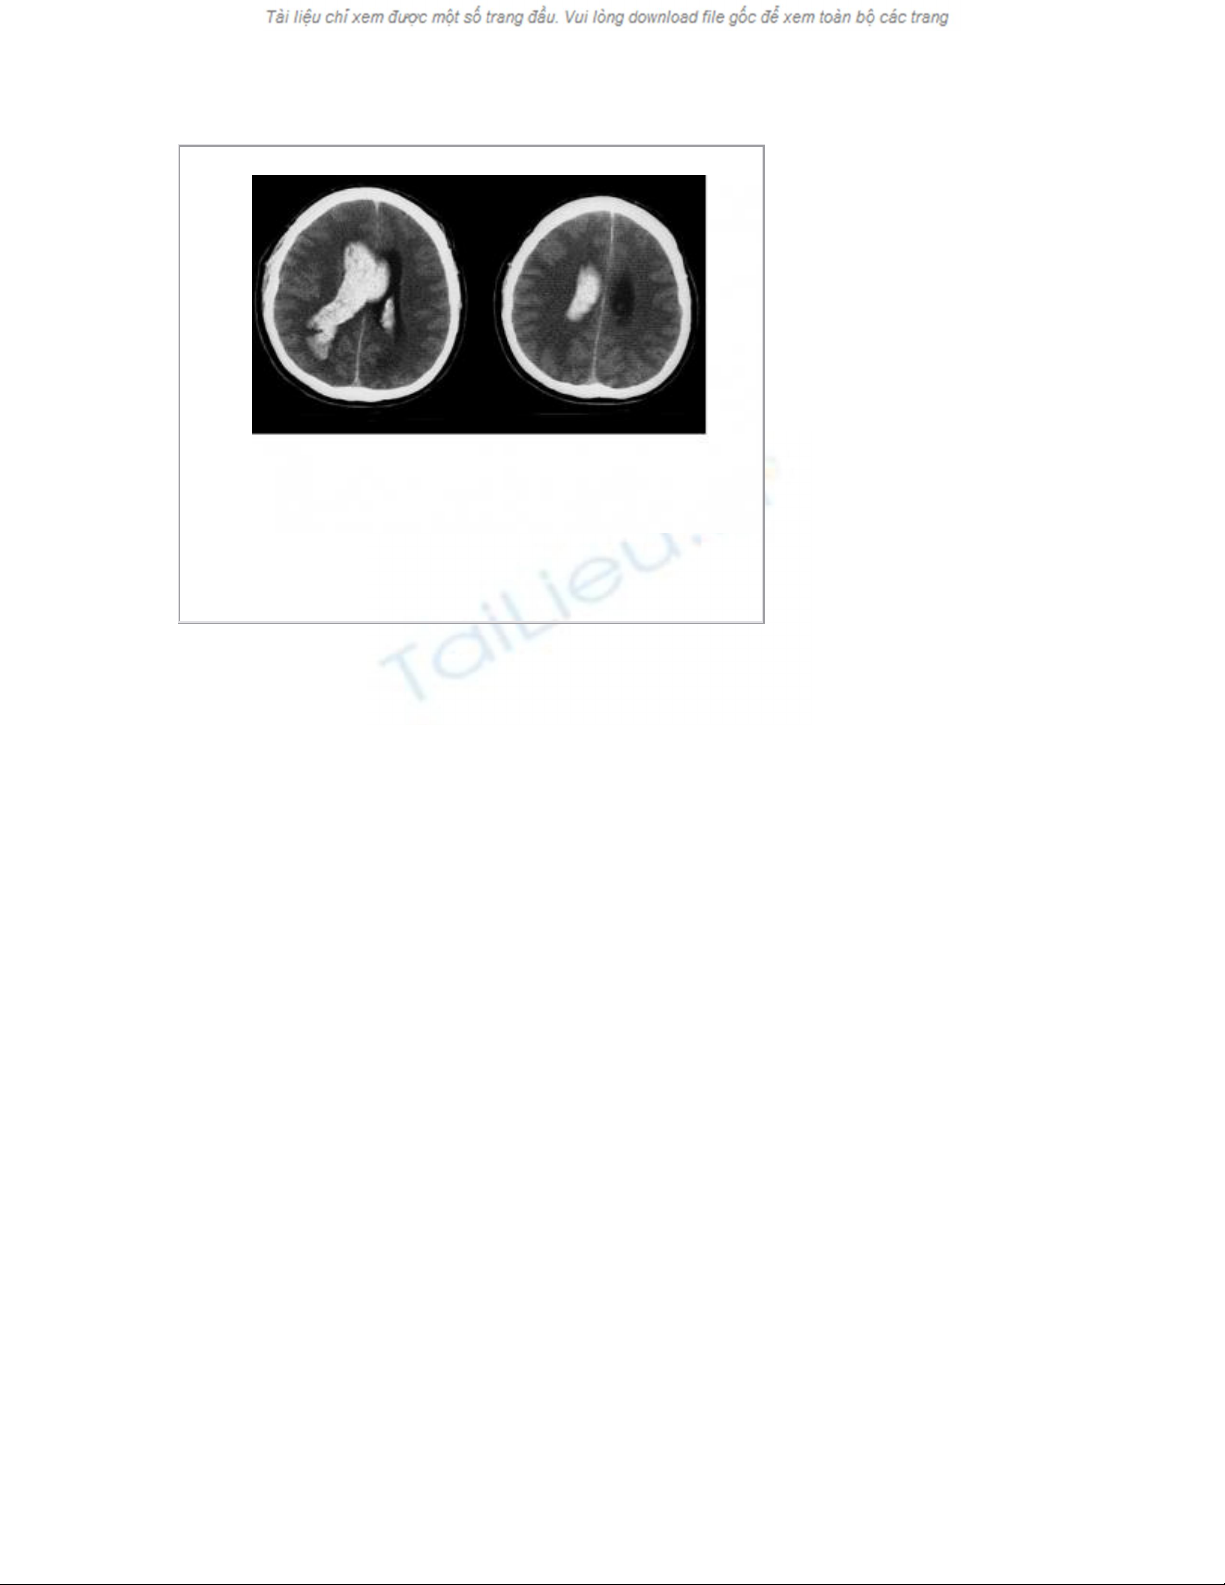

- chuẩn đoán xác định bằng chụp cắt lớp vi tính sọ não ,đôi khi phải

chụp cộng hưởng từ sọ não .